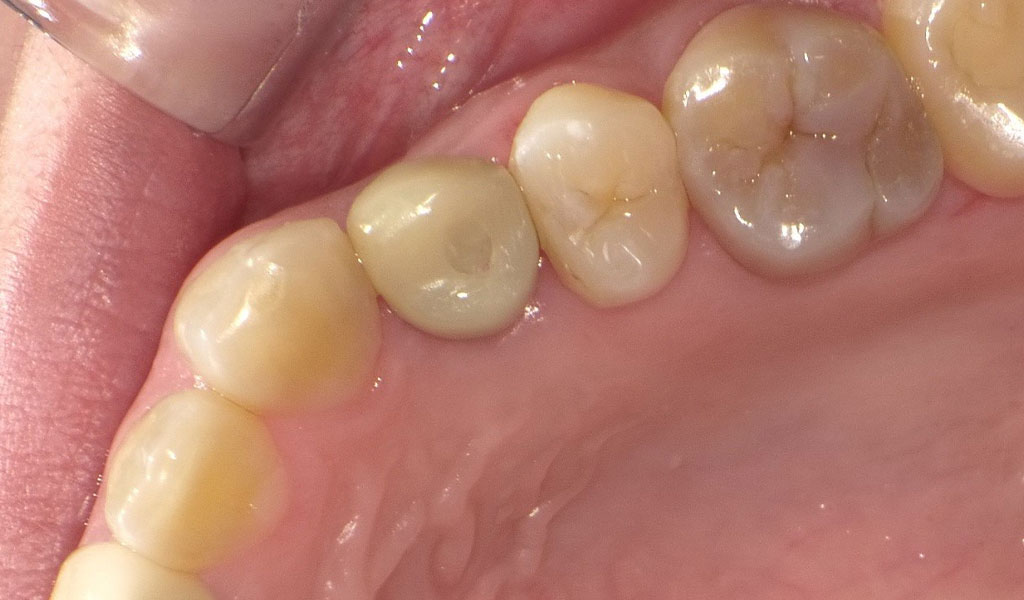

Before1

After1